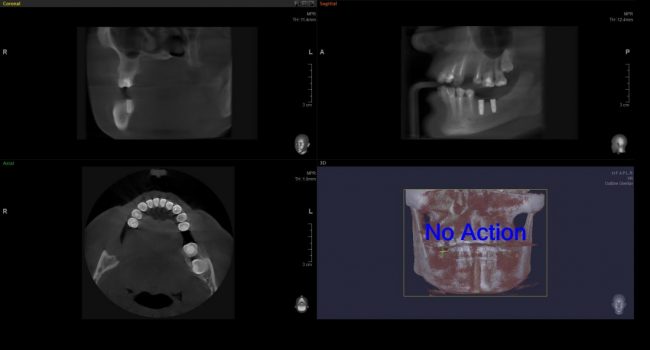

Обследование? Ну, в нашей клинике мы точно так же можем сделать компьютерную томографию (3D объемный снимок). Причём, наше оборудование специально предназначено для изучения зубочелюстной системы, даёт минимальное облучение при высочайших точности и разрешении снимка.

А для того, что ортопантомография (ОПТГ, обзорный или панорамный снимок зубов), является плоскостным, а значит происходит наложение каждой детали снимка послойно друг на друга. Следовательно, рассмотреть объект исследования, в частности, область зуба мудрости, расположенного рядом нижнечелюстного нерва, во всех плоскостях, под иным углом или другой проекции невозможно. КЛКТ (Конусно-лучевая компьютерная томография), напротив дает нам такую возможность.